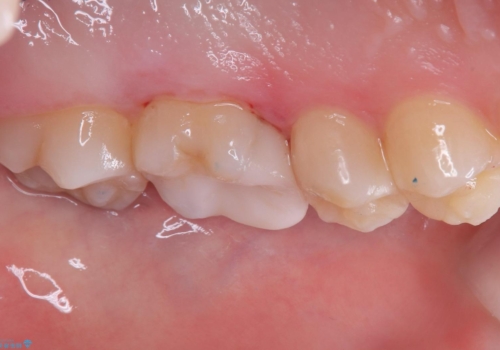

適合性、審美性、材料安定性からセラミックインレーでのやり替えとなりました。う蝕を除去いていくと、残存歯質が薄く破折リスクの高い部位が出てきたため患者さんにも説明し、アンレー窩洞としました。

セラミックアンレー接着時は、ラバーダム防湿を行っています。